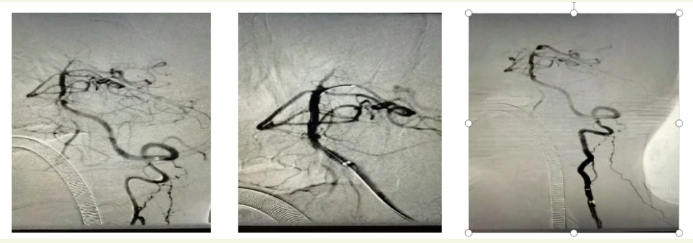

术前DSA技术

手术伊始,神经内科团队运用经股动脉入路脑血管造影技术(DSA),从股动脉插入特殊导管并注入造影剂,清晰呈现血管状况。通路建立后,用微导丝、6F鞘等将2.5×12mm球囊送至闭塞段,采用基底动脉球囊扩张技术对狭窄部位进行两次扩张,同时整合了SWIM技术,放置支架抓取血栓并配合导管抽吸取栓,成功清除大部分血栓。

第一次抽吸后,虽然大部分血栓被成功清除,但血管内的情况发生了变化,血管壁褶皱、分支处可能还隐藏着残余血栓。若不彻底清除,会持续影响血管的正常供血,导致患者病情反复,甚至再次危及生命。神经内科团队决定采用二次抽吸技术,迅速依据实时造影迅速判断残余血栓情况,在已操作过的血管内进行第二次抽吸,精准吸出8cm血栓。

抽吸结束后,发现基底动脉下段可见斑块伴严重狭窄,球囊扩张

江顺福表示,完成抽吸后造影发现基底动脉下段仍存在问题,遂利用同轴输送技术成功植入椎动脉支架,解决血管狭窄问题,历时1.5小时,顺利完成手术。